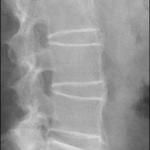

背痛和僵硬的另一个原因:强直性脊柱炎

强直性脊柱炎(AS)是一种进行性慢性炎症性疾病,导致脊柱严重僵硬和丧失活动范围。AS是一种影响脊柱的系统性、风湿性、进行性慢性炎症性疾病,男性比女性多见(3:1)。AS的确切原因尚不清楚,但遗传和环境因素[…]